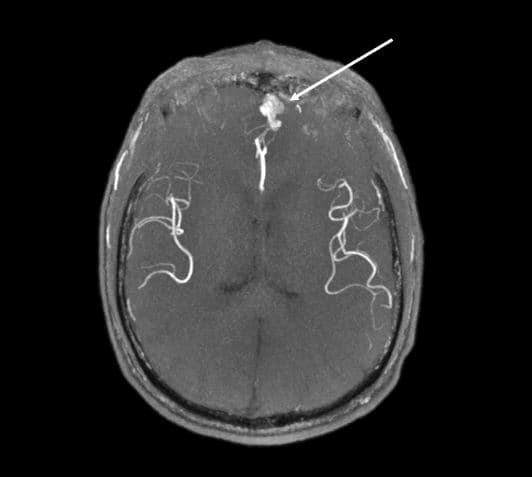

Asymptomatisk cerebral arteriovenøs malformation (pil) hos en 69-årig patient med hereditær hæmoragisk telangiektasi. Gengivet med tilladelse fra patienten.